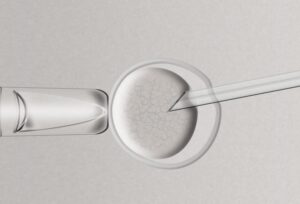

The need for new reproductive technologies is severe and pressing

Decoding the Mysteries of Ovaries